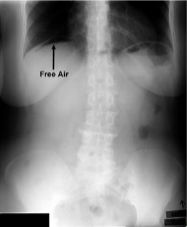

presence of air in peritoneal cavity

pneumoperitoneum

Must have horizontal beam with ride side up to see

free air

In AP Upright(or PA), AP/PA left lateral decub, lateral dorsal decub, you can see